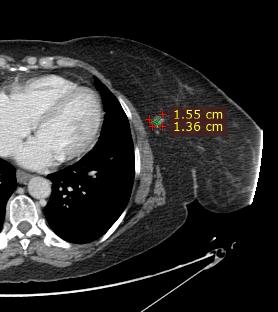

Rolul CT-ului în managementul cancerului rectal

Tomografia computerizată (CT) este una dintre primele investigații imagistice recomandate după confirmarea diagnosticului de cancer rectal. Aceasta poate oferi și unele informații despre invazia tumorală locală, dar rolul ei principal astăzi constă în evaluarea extensiei la distanță a bolii, fiind excelentă pentru identificarea metastazelor pulmonare și hepatice. CTul permite o evaluare rapidă și detaliată a cavității abdominale și toracice, având un rol cheie în stadializarea TNM (Tumor, Node, Metastasis) a cancerului.

Metastaze pulmonare. Examen CT multislice, fereastră pulmonară, plan axial.

Din colecția Centrului de Imagistică, UMFCV